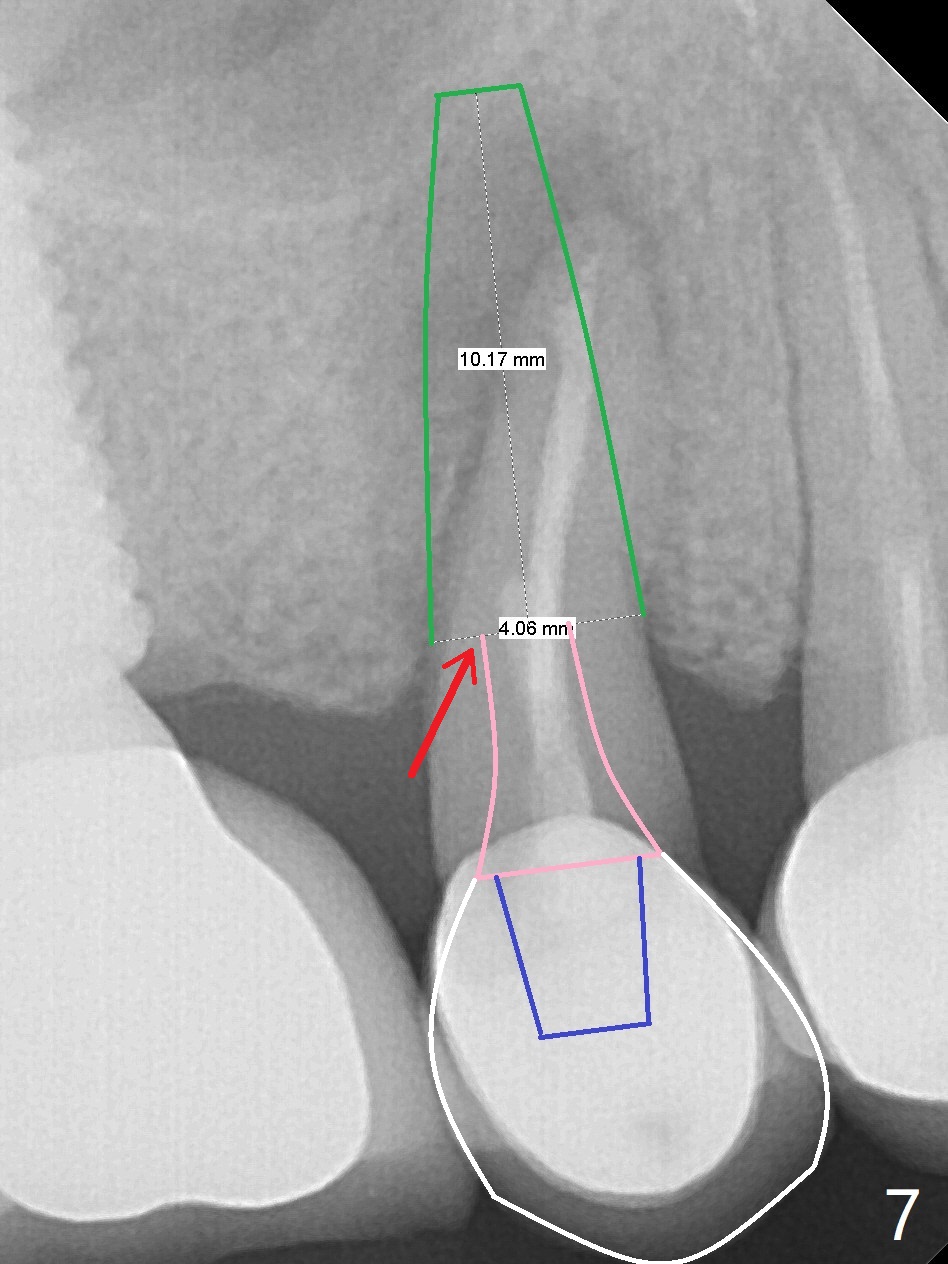

Crown/Implant Ratio

A 53-year-old man has signs of bruxism (Fig.1 diastema *) and root fracture or RCT failure at #4 (Fig.4 (large PARL *)). The RCT failure is related to overload of the affected tooth, which is in turn partially due to infraocclusion of the neighboring implant crown (Fig.1 arrows (implant positioning not ideal)) and partially to due to partial edentulism (Fig.2 missing teeth #14 and 18). For long term, limited ortho will be performed to upright and distalize the tooth #15 (Fig.3 arrow), followed by implants at #14 and 18. For now, the tooth #4 will be extracted (Fig.5), followed by osteotomy in the distal slope of the socket with guide (Fig.6 to get good trajectory). To place a bone-level implant (Fig.7 green), an abutment (blue) with long cuff (pink) is to be used. With poor implant/crown (white) ratio, stress occurs at the junction of the implant/abutment (red arrow), resulting in easy abutment screw loosening. In contrast, stress may be applied to directly to a tissue-level implant (Fig.8 arrow) with less likelihood of abutment screw loosening. The implant/crown ratio improves by approximately 5.5 mm. The roots of the teeth #15 and 16 are so close to each other that interference may occur when the tooth #15 is being uprighted (Fig.9). The empty socket of the tooth #4 is wide buccopalatal (Fig.10); the buccal plate is resorbed coronally (Fig.10 <) so that a 4.5 or 5 mm diameter implant should be placed palatal (Fig.11). Use sticky bone to repair the buccal plate defect and PRF membrane or plug for sinus lift. Following #15 uprighting and distalization, a 5x10 mm implant will be placed at #14; the ridge is triangular (Fig.12 <) so that bone trimmer is needed. A 10 mm long implant will be placed at #18 (Fig.14) to avoid perforating to the submandibular fossa (Fig.13 *).